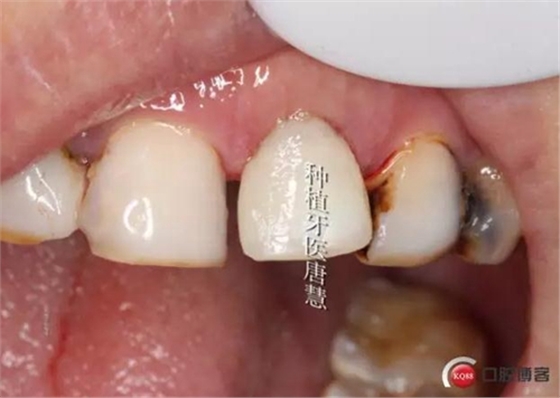

完成臨時(shí)修復(fù)